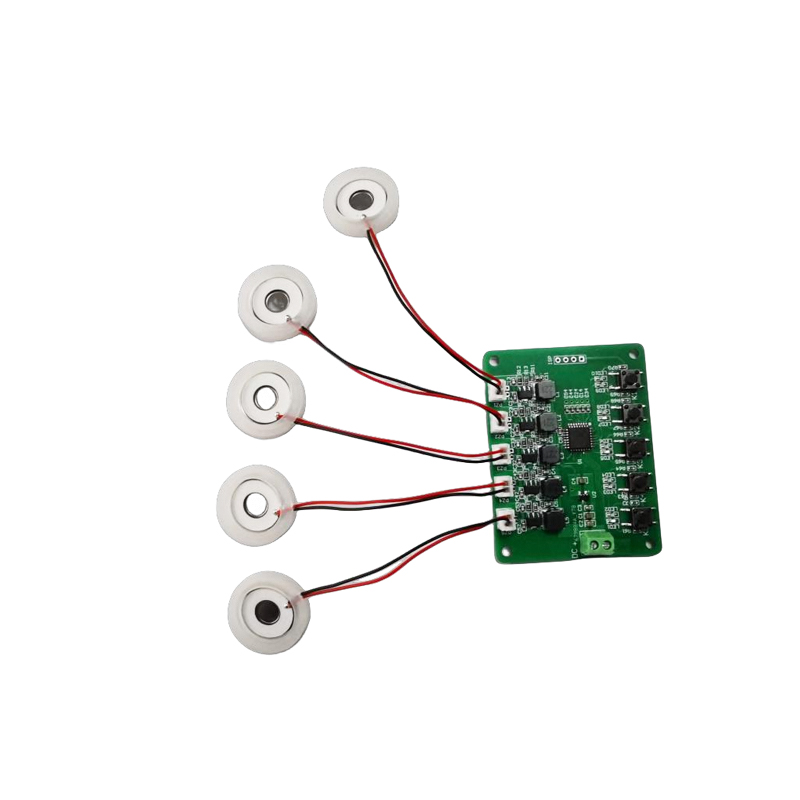

Medical Mesh Nebulizer Tablets zijn precisiecomponenten die in medische apparaten worden gebruikt om medicijnen of oplossingen om te zetten in kleine aërosoldeeltjes voor de behandeling van verschillende ademhalingsaandoeningen zoals astma en chronische obstructieve longziekte (COPD), enz. door inhalatie. Het ontwerp en de materiaalkeuze van het vernevelblad zijn van cruciaal belang om een effectieve medicijntoediening en comfort voor de patiënt te garanderen. De roestvrijstalen membraanplaat wordt met duizenden kleine gaatjes van 2-3 μm in de staalplaat geponst door middel van laserboortechnologie in een nauwkeurig laserproces, en vervolgens wordt het stevig verbonden met de piëzo-elektrische keramische ronde plaat, die de resonantiefrequentie van de piëzo-elektrische plaat omzet in hoogfrequente trillingsenergie via het uitgangssignaal van de PCB-stuurkaart, en de vloeibare medicatie snel afbreekt. in fijne aërosoldeeltjes. Deze druppeltjes worden ook wel de gemiddelde deeltjesgrootte genoemd. Wanneer het gemiddelde D50-percentage van de deeltjesgrootte >60% of meer bereikt, zullen de deeltjes klein genoeg zijn om met ademhaling diep in de longen tot aan het oppervlak van de longblaasjes te kunnen reiken, waardoor de absorptie-efficiëntie van de medicatie en het therapeutische effect worden verbeterd. Medical Mesh micro mesh vernevelaarblad heeft voornamelijk verschillende vormen, roestvrijstalen micro mesh vernevelaarblad, nikkel palladium medische vernevelaarblad, PI-polymeer medische vernevelaarblad, enzovoort. Al het bovenstaande gebeurt via de piëzo-elektrische keramische trillingsenergieconversie om het vernevelingseffect te bereiken.

Ultrasone verstuiver is een apparaat dat het principe van ultrasone trillingen (energieconversie) gebruikt om vloeistof in kleine druppeltjes om te zetten. Het werkingsprincipe is de unieke piëzo-elektrische eigenschappen van de piëzo-elektrische keramiek van de beslissing, het vernevelingsstuk bij de ontvangst van bijpassende excitatie van het elektrische veldsignaal zal de overeenkomstige oscillatiefrequentie produceren, door de rol van hoogfrequente trillingen van de vloeistofcavitatie die van het wateroppervlak wordt weggegooid om een soort watermistdeeltjes te produceren, verstoven met een groot aantal negatieve ionen en kleine deeltjes moleculen, kan bereiken een toename van de luchtvochtigheid, de rol van frisse lucht. Het oppervlak van de verstuiver is bedekt met glasachtig email bij een hoge temperatuur van 800 graden om de zilveren elektroden van de piëzo-elektrische plaat te beschermen, de zuur- en alkalibestendigheid en oxidatieweerstand van de verstuiver te vergroten en de levensduur van de verstuiver te verlengen. Op grote schaal gebruikt in luchtbevochtigers binnenshuis, luchtreinigers, behandeling met medische vernevelaars en schoonheidsauto's, e en andere gebieden, maar ook geschikt voor magazijnen, fabrieken, bevochtiging, desinfectie, om de atmosfeer van bevochtigingsapparatuur te creëren. Fogging-tabletten worden voornamelijk gebruikt in industriële bevochtiging, medische verneveling, aromatherapie-verneveling, omgevingsbevochtiging, tuinverneveling en andere scènes.